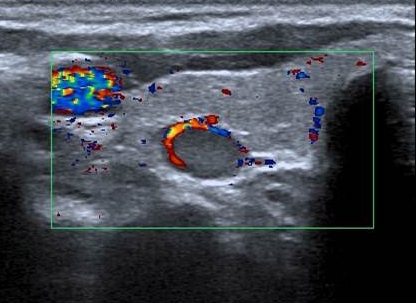

¿Qué patología identifica el signo del arco vascular?